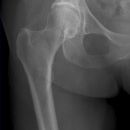

Hüftgelenk a.p.

Indikation

Cave: selten isoliert, meißt mit Luxation oder Azetabulum# kombiniert), Hüftgelenksluxation

Beurteilungskriterien

- CCD- Winkel (120-130°) Spongiosaarchitektur, Trajektorienverlauf im Schenkelhals (Cave: Bei nicht dislozierten SHF Diskontinuität der Trabekel oft einziges Frakturzeichen!)

- Shenton´sche Linie (Harmonischer Bogen aus kaudaler Schenkelhalskontur und der kranialen Zirkumferenz des For. obturatum)

- Gelenkstellung, Gelenkspaltweite (4-5mm nach medial, 3-4mm nach kranial), Luxation => Hüftkopf in ap und axialer Aufnahme in Azetabulum zentriert? Hüftkopfrundung?

- Azetabulumfraktur: vorderer und hinterer Pfannenrand, Pfannendachkontur, Köhlersche Tränenfigur, ggf. Zusatzaufnahmen (Ala- und Obturatoraufnahme), sowie CT

- medialer Azetabulumdachbogen (45° von der Hüftkopfmitte ausgehend nach vorne (!); Teil der lasttragenden Zone des Azetabulums, vgl. Obturatoraufnahme)

- Trochanter major et minor (Abriss, pertrochantäre #?)

- Weichteilzeichen (Fettstreifen medial des M.gluteus minimus zw. M.glutaeus minimus und medius, medial des M.iliopsoas; Konturschatten des M.obturatorius int.)

- med. Schenkelhalsfrakturen nach Pauwels I-III und nach Garden I-IV (2)

- SHF und Pertrochantere Frakturen AO-Klassifikation

- Lokalisation mediale, laterale, pertrochantäre und subtrochantäre Schenkelhalsfraktur

- Hüftgelenksluxation

- Hüftkopffrakturen nach Pipkin

- Einteilung der medialen Schenkelhalsfrakturen nach Pauwels:

Pauwels I°: Winkel zwischen Horizontalen und Frakturlinie < 30°

Pauwels II°: zwischen 30° – 70°

Pauwels III° : > 70°